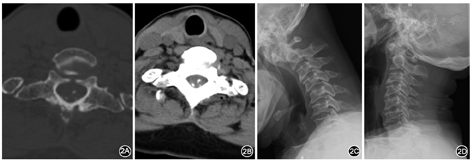

女性,66岁,因"行走不稳7年,双下肢麻木无力加重1周"于2018年6月8日入院。患者7年前无明显诱因出现行走不稳,转身困难;1周前出现双下肢麻木、无力,不能行走,双上肢无明显症状,无明显排便、排尿困难或大小便失禁,无鞍区麻木、晨僵,无关节红肿、发热畏寒等,否认既往头颈部外伤史。患者症状持续不缓解,遂于我院就诊。体检:右侧肋弓以下痛觉减退,左侧胸骨角平面以下痛触觉减退,双下肢位置觉消失,会阴部痛触觉减退不明显,两侧上肢肩外展、屈伸肘、伸腕、握拳及小指外展肌力均为Ⅴ级,两下肢屈髋、伸膝、足背伸、踇背伸及跖屈肌力Ⅱ级,双上肢肌张力无明显增高或降低,两下肢肌张力稍增高,双侧肱二头肌腱反射(++),双侧肱三头肌腱反射(++),双侧膝腱反射(+++),肛门反射(+),双侧Hoffmann征阴性,双侧Babinski征阳性。脊柱MRI检查结果示:颈椎生理曲度反弓,颈椎退行性改变,寰齿关节前间隙增宽,寰枢椎脱位,压迫相应颈髓;C7椎体向前滑移;C6~T1水平黄韧带区域占位性病变,呈T1WI低信号、T2WI高信号,考虑囊肿,椎管狭窄,相应颈髓受压、信号增高(图1)。脊柱CT平扫示:占位性病变内可见散在点状钙化。颈椎动力位X线片示:寰枢椎明显不稳。过伸位X线片示:寰枢椎脱位可复位(图2)。实验室检查:类风湿因子、抗溶血链球菌O、免疫球蛋白(IgG、IgM、IgA)、补体C3及C4、抗核抗体、抗中性粒细胞胞质抗体均呈阴性,血尿酸未见明显异常。诊断:(1)退行性寰枢椎脱位(可复性);(2)C6~T1水平椎管内硬膜外占位:黄韧带囊肿?(3)C7椎体滑移Ⅰ度;(4)不完全截瘫。因患者同时存在退行性寰枢椎脱位与C6~T1水平椎管内占位,均对颈脊髓造成明显压迫,考虑患者不完全截瘫由C6~T1水平椎管内占位所致可能性较大,但不能完全排除寰枢椎脱位影响,故于2018年6月19日在全身麻醉下行"颈后路寰枢椎脱位切开复位,椎弓根螺钉内固定术"及"颈后路C6~T1水平椎板切除及椎管减压,椎管内硬膜外占位切除,椎弓根螺钉内固定术"。术中在切除病变水平椎板后发现此处黄韧带增厚明显,可见囊肿样病变组织位于黄韧带内,被黄韧带包裹,压迫脊髓,椎管明显狭窄,病变与邻近小关节间无接触及交通。术中小心地从硬膜外剥离并完整切除病变组织及周围黄韧带,此过程中增厚的黄韧带与硬膜囊无明显粘连。体外切开病变组织见其内含凝胶样黏液,囊壁与黄韧带粘连紧密,较难分离,提示病变组织起源自黄韧带。术后复查X线片及CT可见颈椎内固定稳固,寰枢椎脱位已复位,C6~T1水平椎管减压充分(图3)。术后病理学检查示:镜下见纤维组织增生,胶原变性,部分区呈囊壁样结构,散在钙盐沉浸,并见少量软骨组织,未见滑膜层,未见异型细胞、尿酸盐沉积。病理学诊断为黄韧带囊肿(图4)。术后2周患者可在搀扶下站立;术后3个月可在搀扶下行走,但步态不稳,双下肢麻木较前有所好转;术后6个月可独自拄支具行走,但双下肢仍有麻木感,较术后3个月时无明显好转;术后9个月随访时患者可独立行走,步态仍不稳,双下肢麻木较前无进一步改善。术后未见明显并发症,患者及家属对治疗过程满意。

黄韧带正常结构可因脊柱退行性病变和持续的微小机械应力而改变[2,3],弹性纤维减少,胶原组织增多,软骨细胞增殖导致软骨样变,并发生钙化增厚[10],黄韧带囊肿可能为黄韧带老化、退变的产物,具体致病机制尚不明确[11,12]。黄韧带囊肿一般位于黄韧带内或部分嵌入黄韧带[3],病理学往往表现为黄韧带与纤维胶原组织退变形成纤维性的厚的囊壁,囊壁上可见钙化点,胶原纤维玻璃样变,弹性纤维破碎,软骨细胞化生,囊内含黄色黏液或凝胶状液体[2,3,5,10]。本例患者术前CT检查即见病变内散在点状钙化,术中见病变组织位于黄韧带内,术后病理学检查可见纤维组织增生,胶原变性,部分区呈囊壁样结构,散在钙盐沉浸,并见少量软骨组织,与之相符。